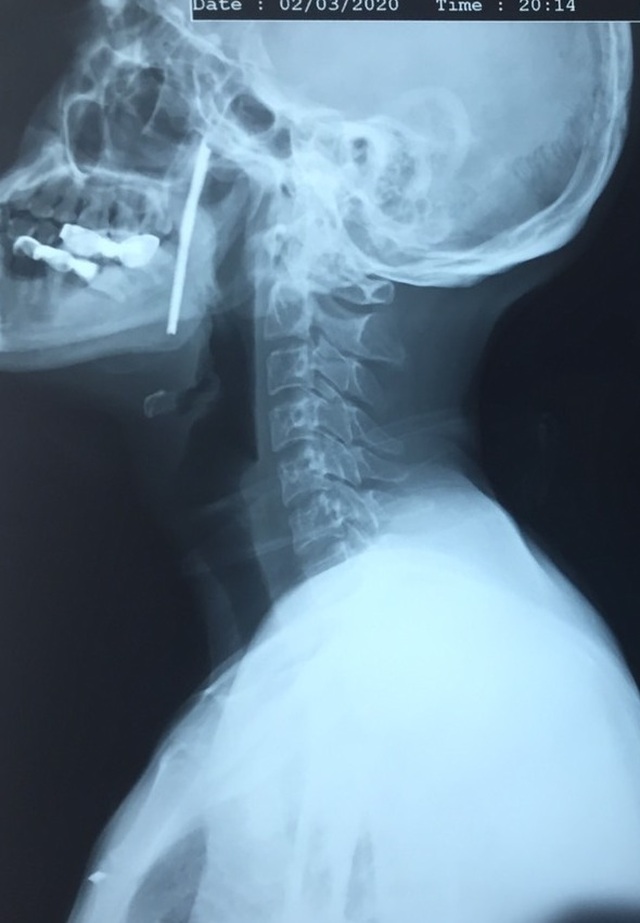

(Dân trí) - Khi được đưa tới Bệnh viện Việt Đức cấp cứu, thanh kim loại dài khoảng 10cm vẫn cắm sâu trong cổ bệnh nhân. Chẩn đoán cho thấy thanh sắt dài xiên từ hầu họng vào trong miệng bệnh nhân.

TS Vũ Ngọc Tú, Trung tâm Phẫu thuật Tim mạch và Lồng ngực, Bệnh viện Hữu nghị Việt Đức cho biết, trên cơ sở phân tích kĩ càng cơ chế ngoại lực, các dấu hiệu lâm sàng thực tế và các xét nghiệm hình ảnh, người bệnh được chẩn đoán vết thương phức tạp vùng cổ, do dị vật kim loại dài, xiên từ hầu họng vào trong miệng.

Điều may mắn cho bệnh nhân, dù thanh sắt xuyên từ vùng hầu họng và miệng, nhưng nó chưa trực tiếp gây tổn thương các thành phần này. Tuy nhiên, việc nằm sát các cơ quan hệ trọng của cơ thể khiến các bác sĩ phải tính toán làm sao lấy dị vật ra nhưng đảm bảo tính mạng người bệnh và xa hơn nữa là giữ được chức năng cơ thể.

Sau quãng thời gian cân não, cuối cùng dị vật kim loại đã được lấy ra, đảm bảo an toàn tuyệt đối cho người bệnh. Đây là thanh kim loại dài hơn 10cm, rất sắc nhọn.

Sau phẫu thuật, người bệnh phục hồi nhanh chóng, không có bất kì biến chứng gì. Hiện tại bệnh nhân đã có thể nói và ăn uống được bình thường, chờ ngày xuất viện.